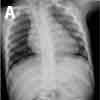

Inspiratory (A), expiratory (B), and lateral (C) chest radiographs confirmed the diagnosis of an endobronchial foreign body. Bronchoscopy revealed a blue pushpin obstructing the right bronchus intermedius and facing proximally into the large airways (D). The larynx, trachea, carina, and left main bronchus were not affected.

Chest radiographs may demonstrate air trapping, atelectasis, or consolidation and are suggestive of a radiopaque foreign body.4 In older children like this patient, chest radiographs should be obtained during inspiration and expiration. Fluoroscopy may be needed in young children. In a 10-year retrospective study, plain chest radiographs revealed a foreign body in only 23.56% of patients.5 In another retrospective study, chest radiographs were normal in 56% of children with tracheal foreign bodies.6